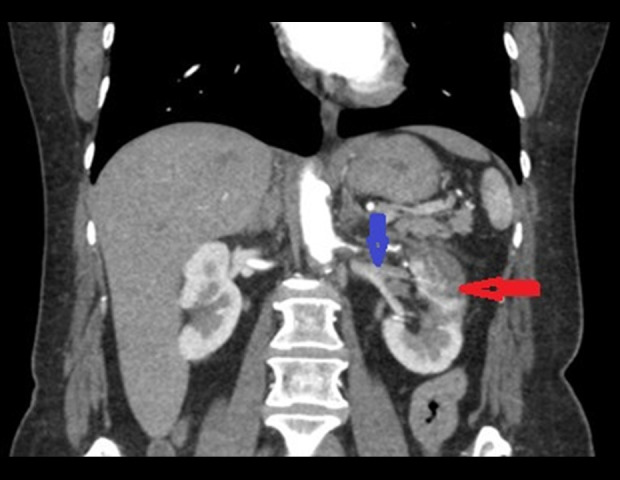

BACKGROUND Renal infarction is a rare condition resulting from interruption of renal arterial blood flow. Its nonspecific presentation often mimics more common diagnoses such as nephrolithiasis, pyelonephritis, or musculoskeletal pain, contributing to delayed or missed diagnosis. Early identification is essential to prevent irreversible renal damage and optimize patient outcomes. Imaging plays a critical role in both the initial diagnosis and in determining the underlying etiology, which may include thromboembolism, in-situ thrombosis, vascular injury, or hypercoagulable states. CASE REPORT We describe a case of a 63-year-old woman with a history of coronary artery disease, diabetes mellitus, hormone replacement therapy, and a 42 pack-year smoking history, who presented with sudden-onset, severe left-flank pain. Initial laboratory results were nonspecific, with mild proteinuria and microscopic hematuria. Computed tomography (CT) angiography demonstrated severe stenosis of the superior left renal artery and extensive left renal infarction. A diagnosis of atherosclerotic renal infarction was made. She was treated with intravenous heparin, transitioned to dual antiplatelet therapy and high-intensity statin, and discharged with a 30-day cardiac event monitor. No arrhythmia was detected, and her thrombophilia workup was negative. Follow-up CT angiography 1 month later revealed complete resolution of the renal artery stenosis, with no residual narrowing or plaque. The transient nature of the vascular finding, along with the lack of structural atherosclerosis, prompted diagnostic reassessment, favoring an embolic mechanism possibly related to multiple modifiable prothrombotic clinical risk factors and unrecognized embolic sources. CONCLUSIONS This case illustrates the importance of follow-up imaging and clinical reassessment in differentiating embolic from atherosclerotic causes of renal infarction.